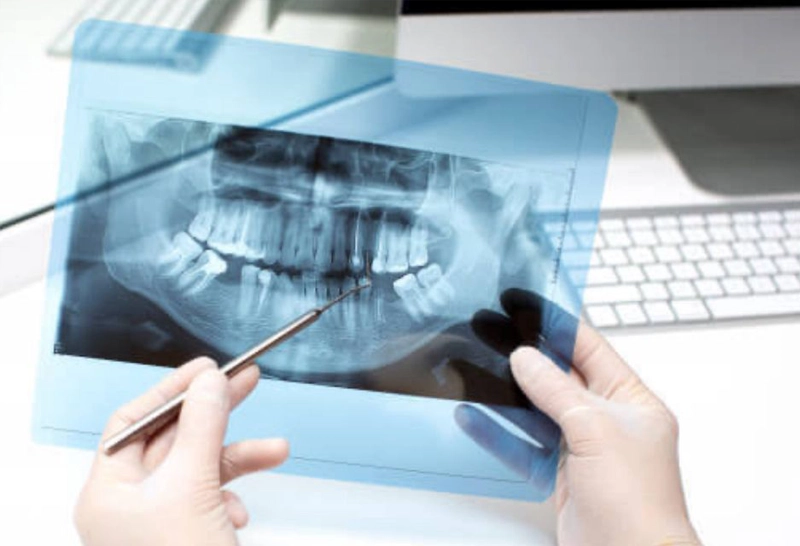

Aulas expositivas dinâmicas com vasto material ilustrativo (imagens radiológicas, tomográficas, ressonâncias, ultrassonografias, gráficos de exames laboratoriais, lâminas histopatológicas).